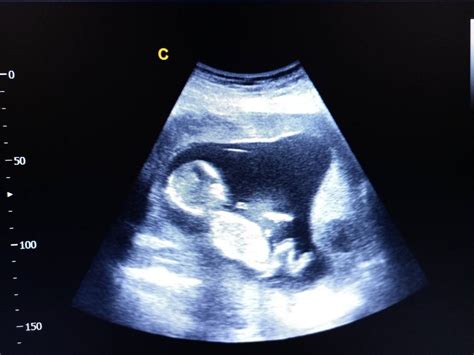

Ecografia de morfologie fetală, cunoscută și sub numele de ecografie morfologică, este o tehnică de investigație medicală imagistică, extrem de importantă, care evaluează și monitorizează sarcina. Morfologia fetală este o investigație ecografică utilizată pentru a monitoriza dezvoltarea fătului. Aceasta are ca scop evaluarea amănunțită a anatomiei și dezvoltării fătului pentru a identifica eventualele anomalii structurale sau de dezvoltare. Ecografia este realizată doar de către medicul cu supraspecializare în medicină materno-fetală între anumite săptămâni de sarcină. Suplimentar, pentru obținerea mai multor informații despre evoluția sarcinii, medicul poate indica și efectuarea unor investigații suplimentare. În plus, morfologia fetală are și rolul de a diagnostica numeroase afecțiuni grave de care poate suferi fătul, inclusiv malformațiile. Ecografia morfo-fetală indică și sexul copilului, dacă părinții doresc să îl afle.

La ecografia morfologică medicul specialist depistează aproape orice afecțiune a fătului, precum și starea placentei și a cordonului ombilical. Pot fi diagnosticate afecțiunile următoarelor organe: creier, inimă, stomac, abdomen și peretele abdominal, rinichi, ficat și altele. În plus, pot fi depistate malformațiile craniene, ale feței, coloanei vertebrale, mâinilor și picioarelor.

Datorită ecografiei morfo-fetale 3D/4D aflăm încă din timpul sarcinii dacă copilul suferă de o malformație gravă sau mai puțin gravă, inclusiv dacă are buză de iepure, îi lipsesc membrele sau are o afecțiune severă la creier sau la coloana vertebrală, precum și dacă copilul îndură consecințele unui sindrom nemilos precum Edwards, Patau sau Down.

Ecografia 3D și 4D reprezintă tehnologii avansate de imagistică utilizate în timpul sarcinii pentru a oferi imagini detaliate ale fătului. Ecografia 3D utilizează ultrasunetele pentru a crea imagini tridimensionale ale fătului. Astfel, se obține o imagine mai clară a structurilor anatomice fetale. Ecografia 4D este o formă avansată de ecografie 3D, care adaugă elementul de timp, oferind imagini în mișcare în timp real. Practic, ecografia 4D creează un video al fătului în mișcare, permițând observarea expresiilor faciale și a activităților fetale în direct.

Comparativ cu ecografia clasică, 2D, cele două variante mai performante au avantajul că oferă imagini mai clare și mai detaliate ale fătului. Astfel, aceste forme de ecografie devin extrem de utile pentru a oferi viitorilor părinți o imagine a ce înseamna malformația fetală descoperită și evoluția acesteia.